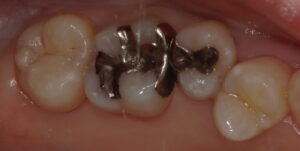

おそらく術前の保険診療では2,3分で詰めたと思いますが、今回この歯は防湿から精密充填まで20分ほどかかっております。

治療回数:1回(約60分)

料金:¥44,000(税込み)